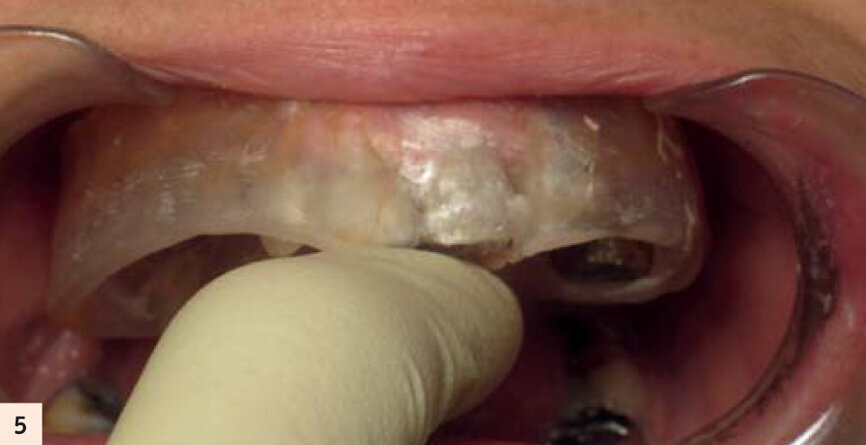

L’important est de reproduire par l’empreinte en fin de chirurgie, l’occlusion enregistrée des semaines auparavant. La technique utilisée sera l’empreinte fractionnée, grâce à une gouttière callée sur des repères fixes que nous retrouvons en fin d’intervention (Fig. 5). Cette méthode a été décrite par Luc Gillot et Bernard Cannas qui font partie des pionniers de la MCI en France.9, 11 Ce cas clinique est complexe. Comme toute chirurgie, nous n’avons pas le droit à l’erreur. La planification sur ordinateur a permis de se familiariser avec les volumes osseux. Simuler la chirurgie permettrait d’éviter les pièges d’une anatomie complexe. En partenariat avec l’équipe Vizua et la Sapo implant, nousimprimons le maxillaire de notre patiente en individualisant les dents pour visualiser les alvéoles d’extraction (Figs. 6 et 7). Puis nous procédons au forage dans ce modèle imprimé en résine, en suivant notre planification. Nous appréhendons les difficultés de ce cas : la fine corticale du bloc incisif, la position exacte de l’implant en 15 dans la paroi antérieure du sinus droit... Quelle meilleure préparation que la simulation sur modèle ? (Fig. 8)

Gouttière pour empreinte fractionnée en fin de chirurgie.